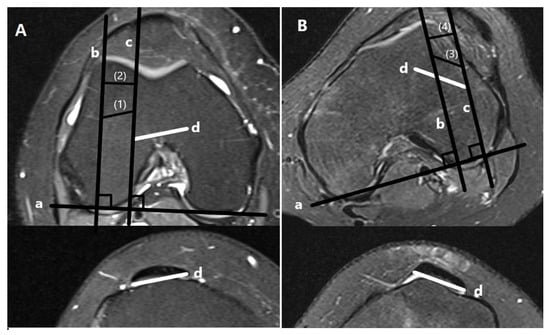

- Lateralization measurements